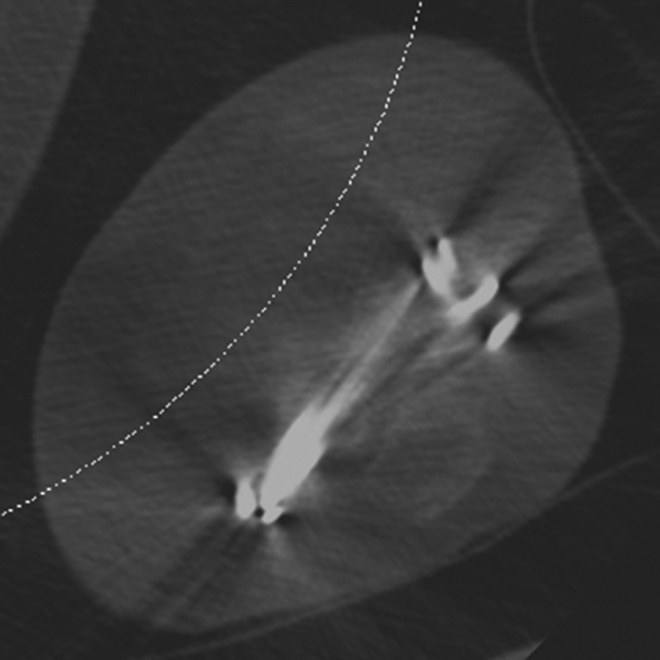

Polyethylene Liner Displacement. Sagittal multiplanar reformation of reverse total shoulder arthroplasty demonstrates posteriorly displacement of low attenuation polyethylene liner relative to the humeral component and glenosphere in patient with limited range of motion.